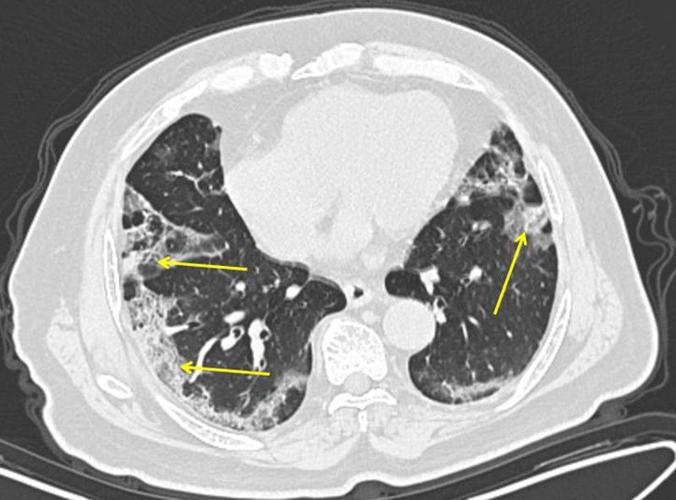

Lung X Ray